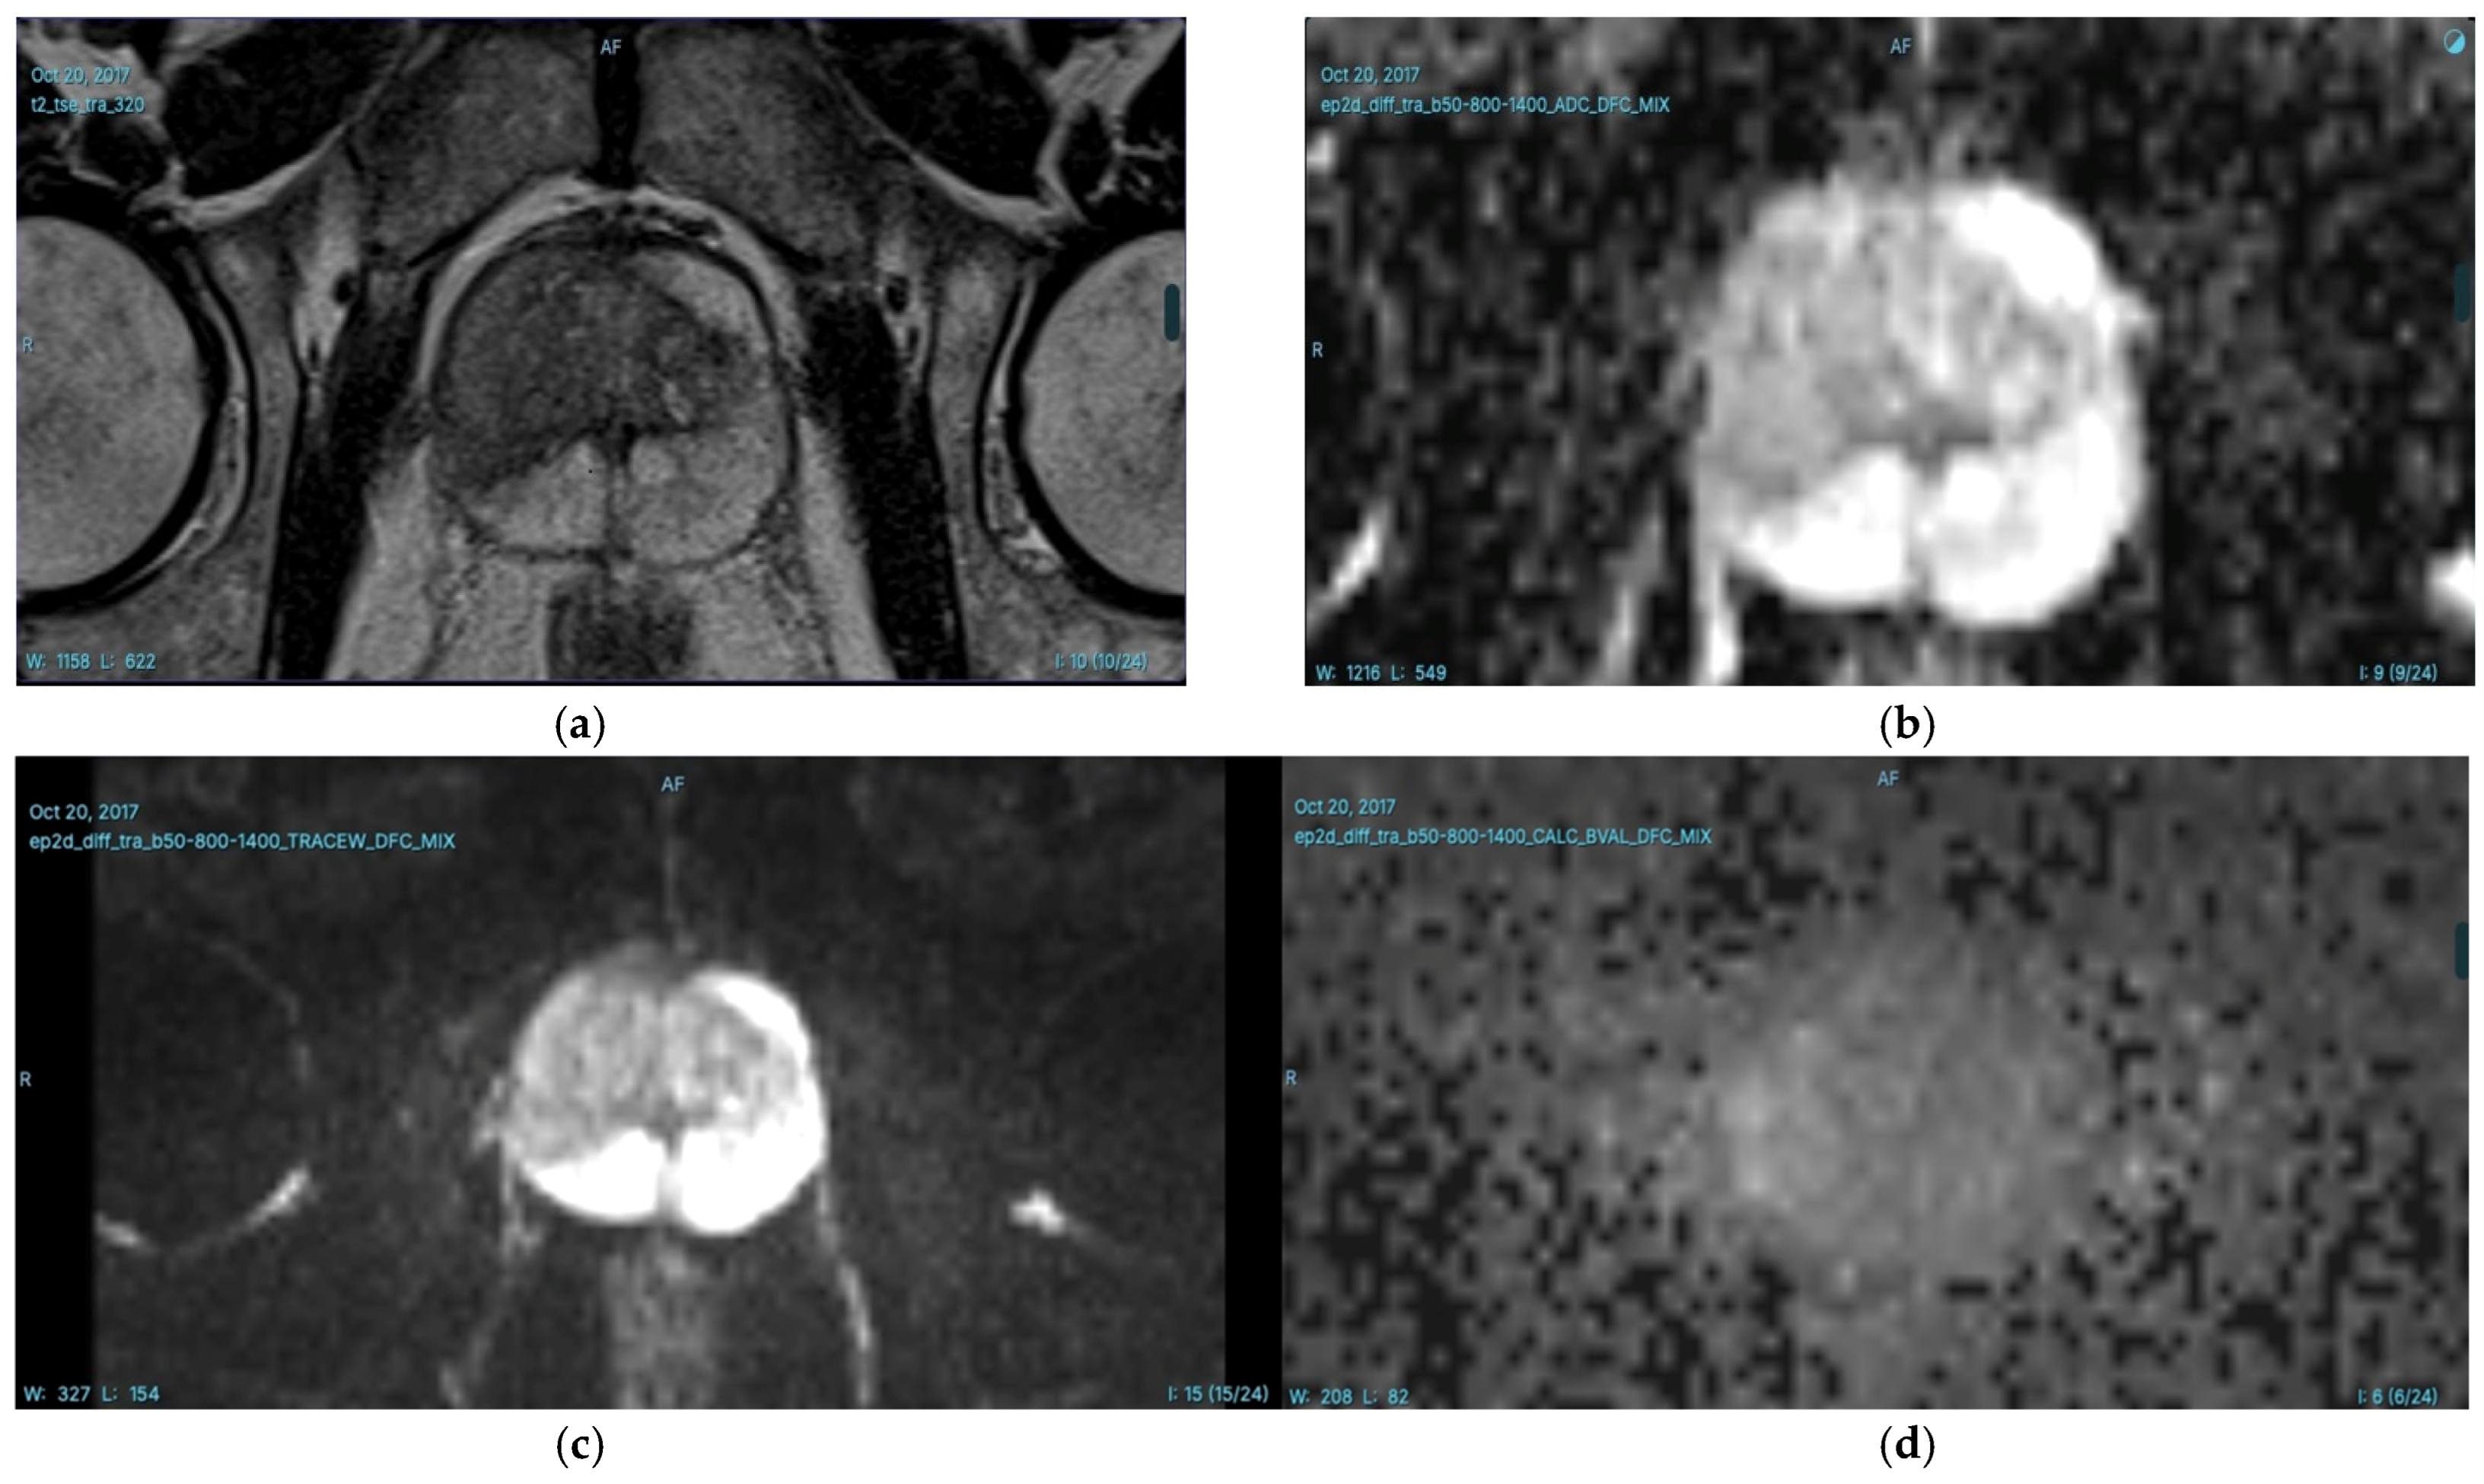

- Hu, L.; Fu, C.; Song, X.; Grimm, R.; von Busch, H.; Benkert, T.; Kamen, A.; Lou, B.; Huisman, H.; Tong, A.; et al. Automated deep-learning system in the assessment of MRI-visible prostate cancer: Comparison of advanced zoomed diffusion-weighted imaging and conventional technique. Cancer Imaging 2023, 23, 6. [Google Scholar] [CrossRef]